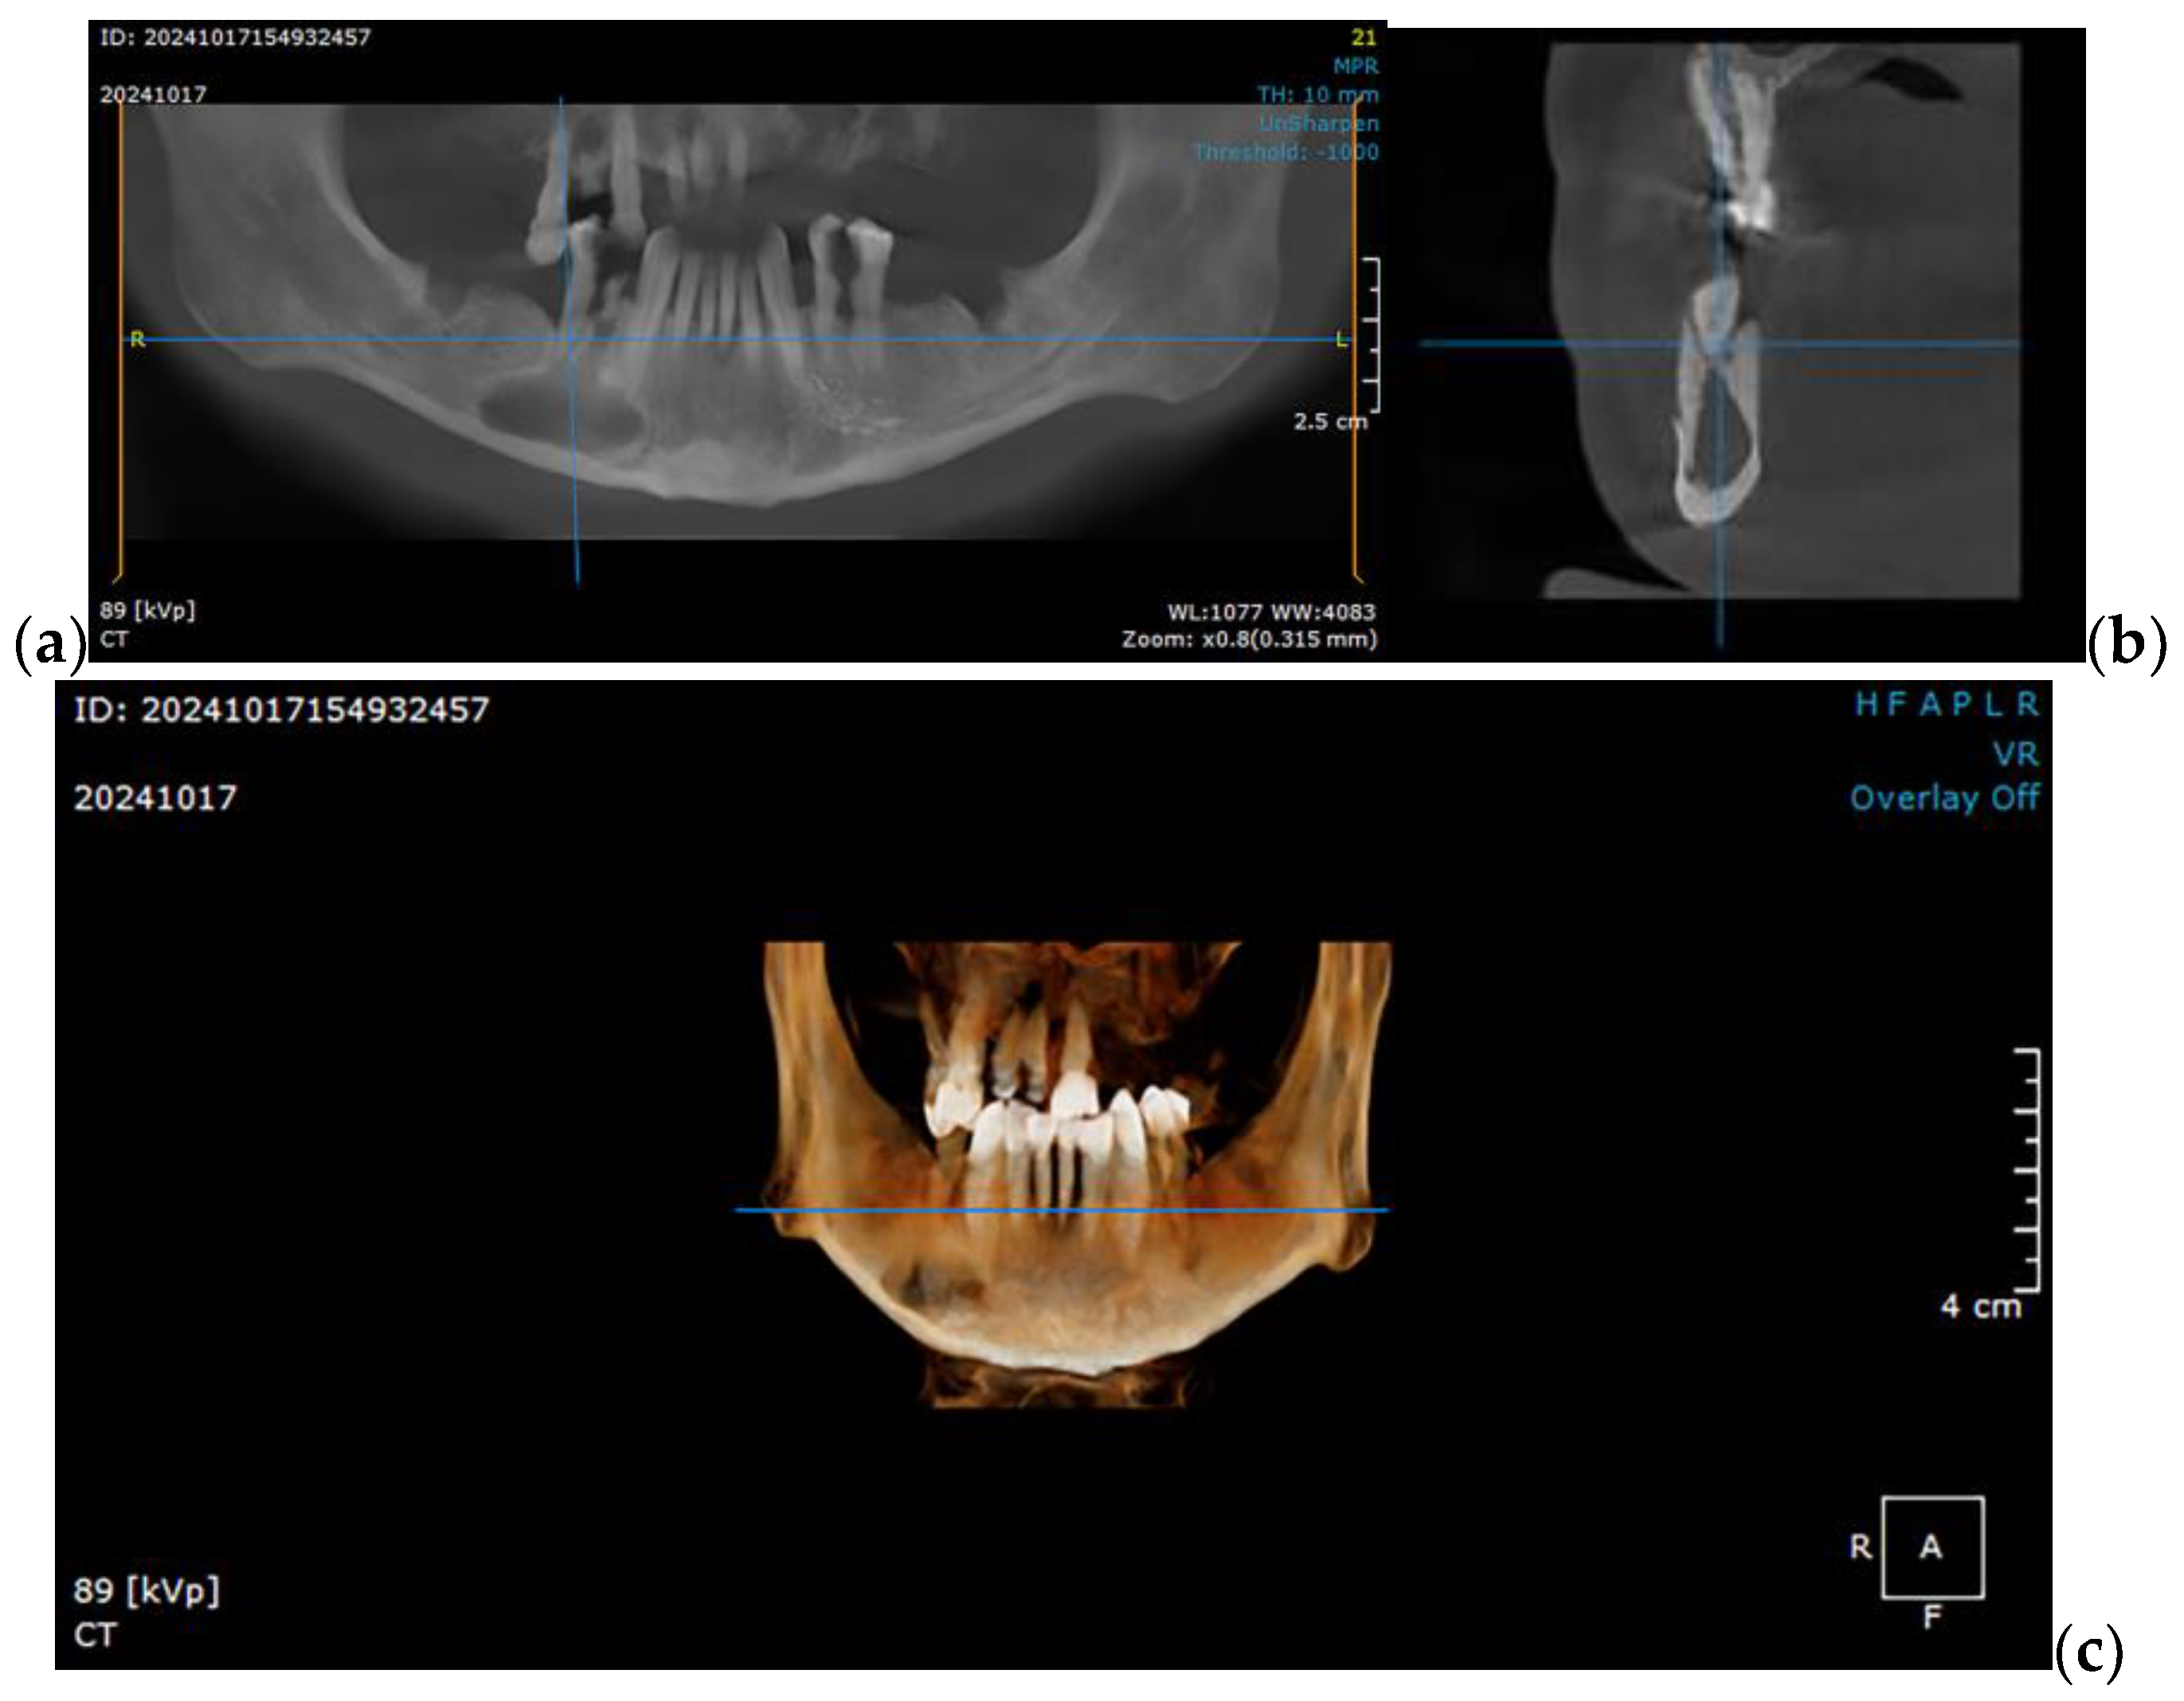

2.1. Optimizing the Mandibular Model for Simulation